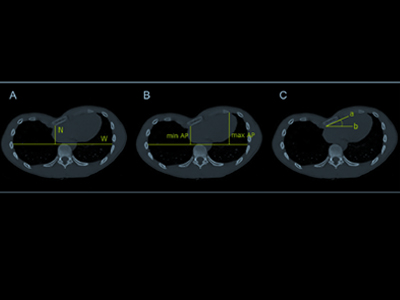

Antecedentes / propósito: Se desconoce el papel de la torsión esternal (ST) en pacientes con pectus excavatum (PEX). Evaluamos la relación entre ST y los índices de malformación torácica y compresión cardíaca (CC). Métodos: se incluyeron pacientes consecutivos con PEX a los que se les realizó tomografía computarizada de tórax y resonancia magnética (RMC) para definir la candidatura quirúrgica. Los índices de malformación incluyeron el índice de Haller (HI), índice de corrección (CI) y ST. La CC y la relación entre el ancho del anillo tricúspide y el anillo mitral se evaluaron mediante RMC.